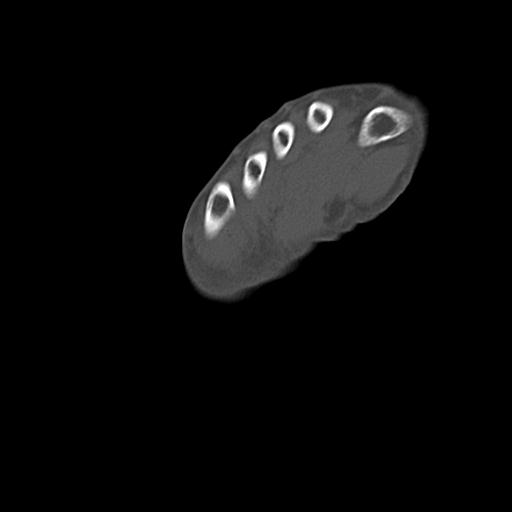

102803 1/12(キウスなし) 1/27 左下腿 4R 30歳女性 左脛骨軸内釘